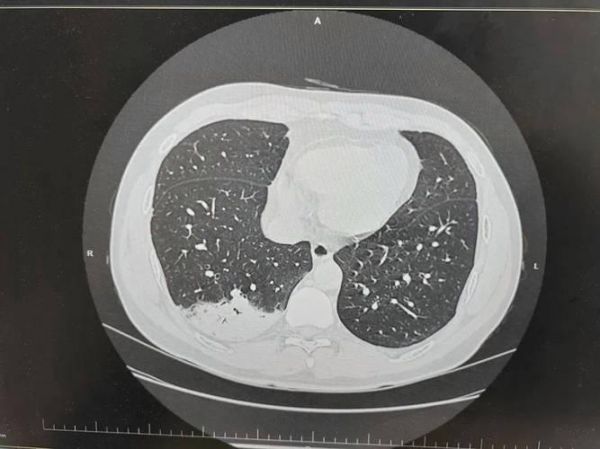

您是否面临“癌症”风险?针对肺癌,我们建议进行胸部低剂量CT检查,这是国际公认的肺癌筛查金标准,比X光更为清晰。若您有长期吸烟史、肺癌家族史或职业暴露于致癌物质,此项检查尤为必要。